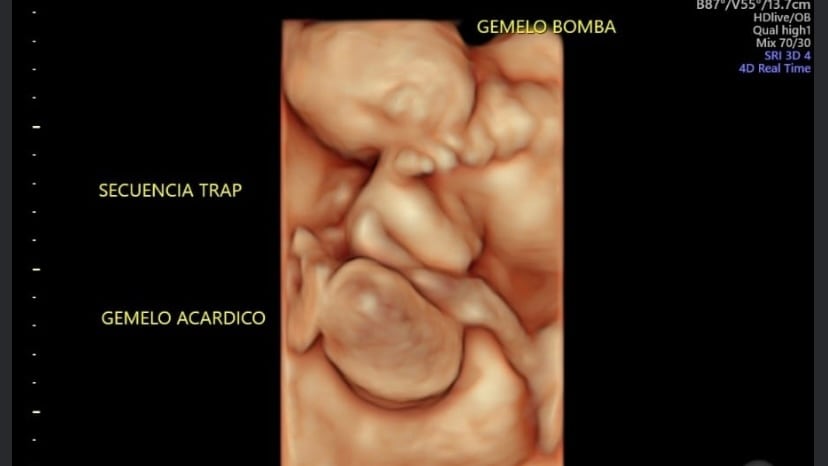

El caso corresponde a una secuencia de perfusión arterial revertida de gemelos o TRAP (del inglés ‘Twin Reversed Arterial Prefusion’). Este tipo de condiciones genéticas ocurre en gemelos que comparten una sola placenta (monocorial), en la cual existe un gemelo con malformaciones severas (el gemelo TRAP) que lo hacen incompatible con la vida. Al gemelo TRAP le suelen faltar el corazón (es acardio) y la cabeza (es acéfalo). En este caso, al feto solo se le formó una extremidad: la pierna.

El cordón umbilical del gemelo TRAP no recibe sangre de la placenta, sino que lo hace directamente su gemelo mediante una comunicación arterio-arterial única de gran calibre establecida con el cordón umbilical del gemelo sano. De esta manera, el gemelo sano es el que envía la sangre (por eso se le llama también gemelo ‘bomba’) al TRAP y lo mantiene ‘vivo’, a pesar de no tener corazón.